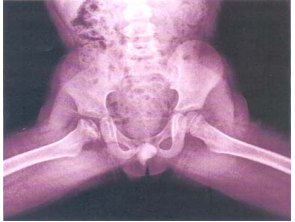

22 7 歲男童因右髖疼痛前來看診,他平常很好動,也經常跌倒。近日家長發現他有時跑步後發生跛行現 象,經 X 光檢查發現如下圖,則其正確診斷應為下列何者?

(A)髖關節半脫位 (B)股骨頭骨壞死 (C)股骨頸骨折 (D)髖關節滑膜炎